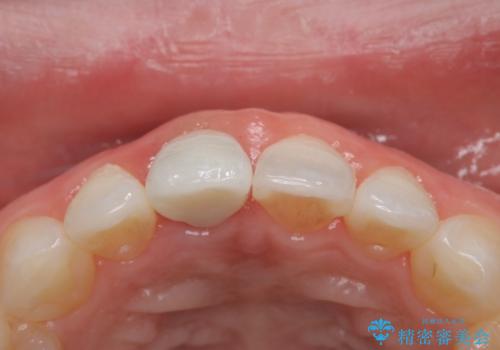

前歯の色が気になる オールセラミッククラウン(SP)

矯正の時使用していた仮歯を新調し、その後最終的な形を作ってから型取りを行います。

色もきれいだと患者様も満足されておりました。